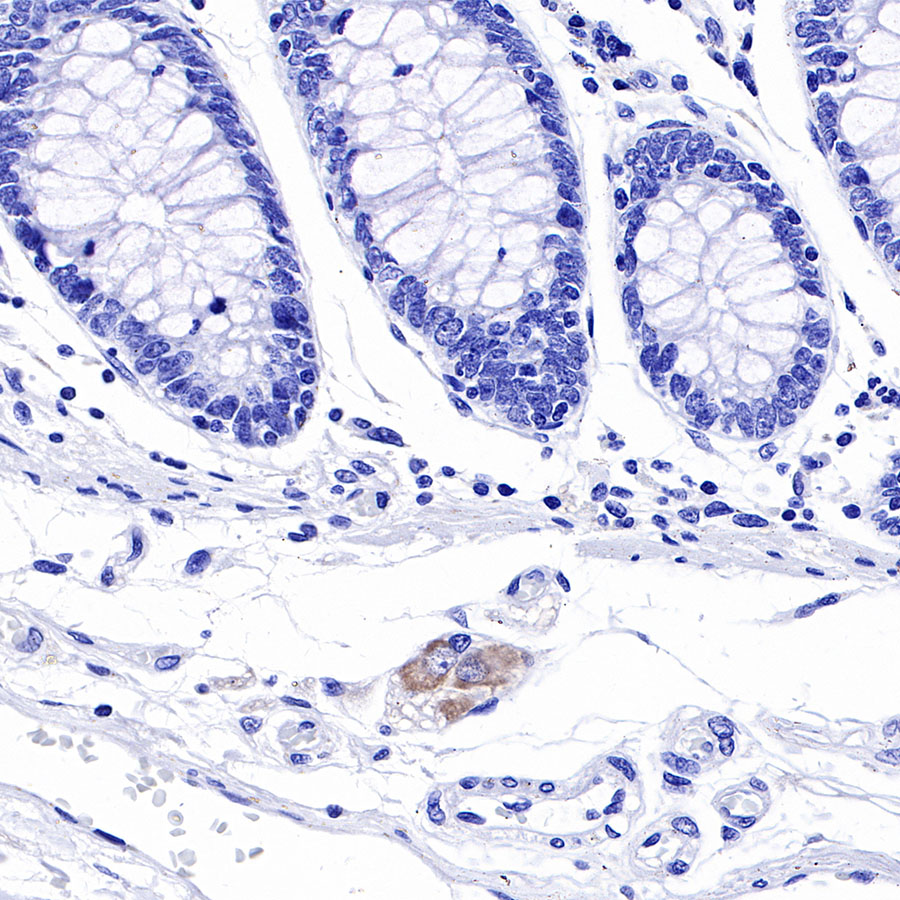

IHC shows positive staining in paraffin-embedded human colon. Anti-Tau antibody was used at 1/2000 dilution, followed by a HRP Polymer for Mouse & Rabbit IgG (ready to use). Counterstained with hematoxylin. Heat mediated antigen retrieval with Tris/EDTA buffer pH9.0 was performed before commencing with IHC staining protocol.